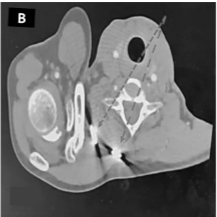

A Rare and Interesting Case of Sciatic Nerve Compression Due to Proximal Femoral Osteochondroma in a Young Adult – A Case Report

Ninad Kishor Honwadkar , Eknath Deosing Pawar , Abhiram T V , Aravind Chanal , Atharva Alaspure